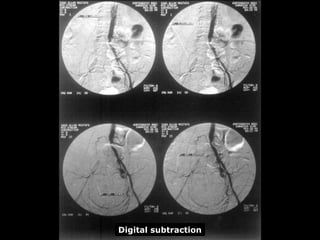

Arteriography

Digital subtraction

1- Laboratory investigations: 2-Imaging: - Doppler flow study. • ABI • Segmental pressure - Duplex scanning - Arteriography Arteriography